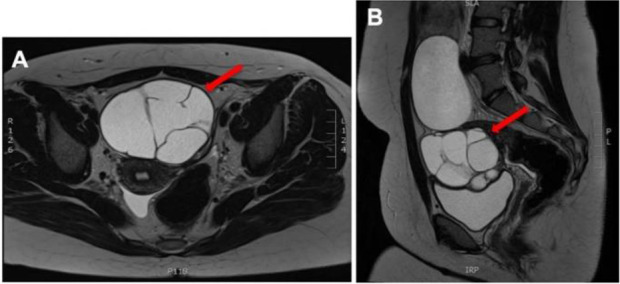

Case presentation: A 16-year-old nulliparous female was admitted with persistent lower abdominal pain and bloating. A pelvic magnetic resonance imaging showed large bilateral cystic and multiloculated adnexal masses arising from her ovaries. Her tumor markers were normal. The patient underwent three seperate ovarian cystectomies over a seven-year period from the age of sixteen due to recurrent large bilateral benign ovarian mucinous cystadenomas. Repeated histological examinations were the same after each case. Given her age and the history of multiple ovarian surgeries, she was referred to the fertility clinic to explore options for oocyte cryopreservation.